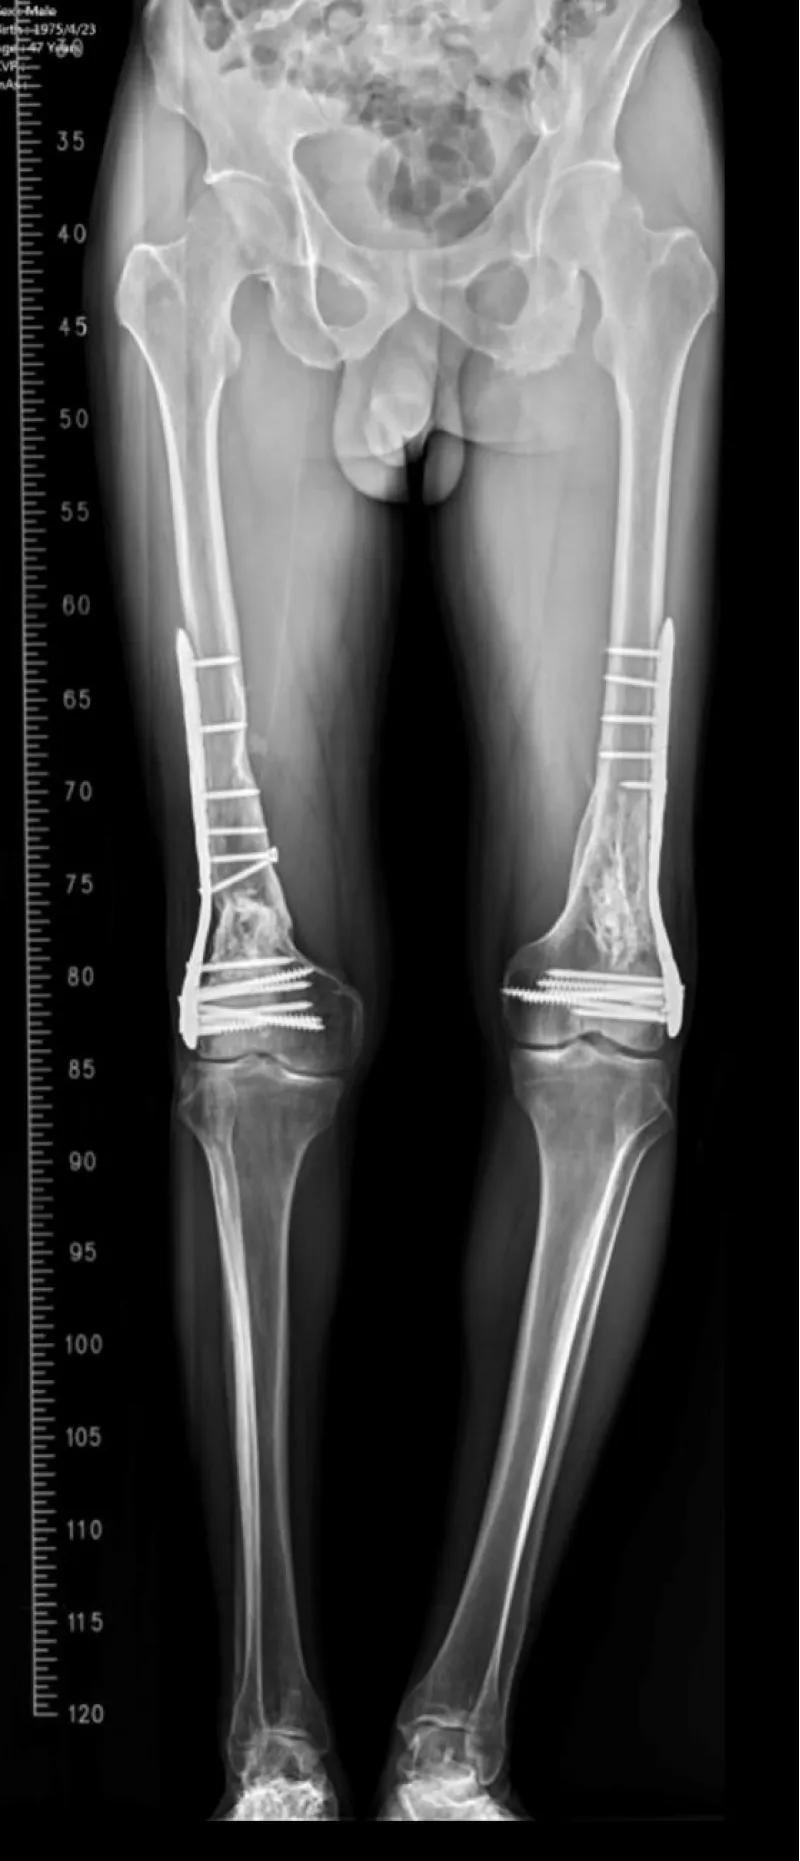

A middle‑aged patient sustained bilateral open distal femur fractures in a high‑energy mechanism (right Gustilo‑Anderson type II; left type I). During pre‑operative resuscitation, the patient developed acute hypoxemia with a unilateral alveolar opacity on the right‑sided lung field. Point‑of‑care lung ultrasound and radiography favored a pleural‑compartment problem over diffuse edema. An ultrasound‑guided 14‑Fr pigtail catheter was placed for targeted decompression. SpO₂ rose promptly and a control radiograph showed re‑expansion. After stabilization, staged definitive fixation (open reduction and internal fixation) was performed. Recovery was uneventful; subsequent long‑leg alignment films demonstrated consolidating callus and functionally symmetric lower limbs.

Figure 1: A–D: Hyperacute unilateral decompensation, 12‑minute rescue, and orthopedic context. A: pre‑intervention chest radiograph with right‑lung opacification/volume loss. B: post‑decompression ~T+12 min (endotracheal tube in situ) with re‑expansion and improved aeration. C: oxygenation trajectory (0–30 min) showing PaO₂/FiO₂ 92→308 within 12 minutes; induction at T+30 min and ORIF at T+90 min. D: representative pre‑operative distal femur views demonstrating bilateral, comminuted metaphyseal–diaphyseal extension. Bedside LUS guided targeted decompression with initial water‑seal to limit early suction and REPE risk [19-22]; small‑bore use aligns with trauma literature [14-16,24]; timing followed EAC once physiology normalized [17,18,23]; the distal femur patterns provide a plausible V/Q amplifier consistent with FES imaging reviews [13].

Figure 2: Pre-operative imaging of distal femur fractures. Representative lateral views demonstrate bilateral open distal femur fractures (right Gustilo‑Anderson II; left I).

Figure 3: Additional pre-operative oblique/lateral projections detailing comminution and distal extension.

Figure 4: Long-leg standing follow-up radiograph confirming alignment and interval bony consolidation after staged ORIF.

At outpatient follow-up, the patient ambulated independently without exertional dyspnea. On examination, the bilateral knee range of motion measured 2°–110° with no extensor lag. Radiographs demonstrated progressive callus with maintained alignment; no readmissions or supplemental oxygen were required.